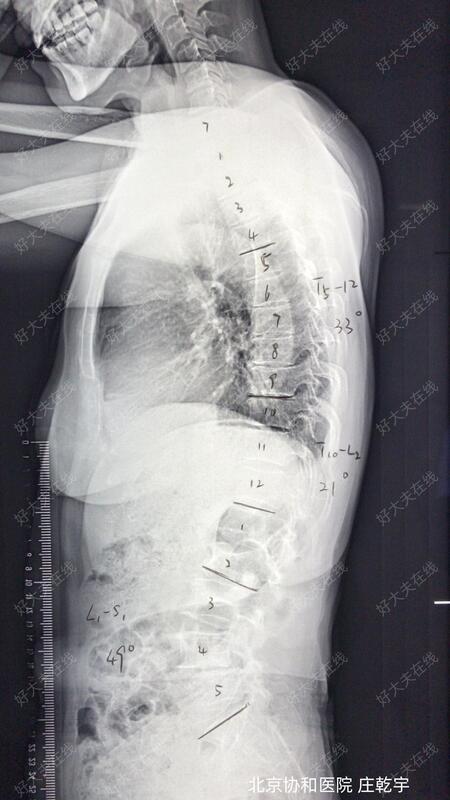

术前X片可见患者退变性腰椎侧弯,L4腰椎滑脱;

术前CT评估即发现腰椎多节段椎管狭窄,L4-5节段黄韧带骨化,硬膜受压明显。

术前设计行L3-5椎管减压、L4滑脱复位、L2-5固定融合;通过腰椎相对短节段固定,在解除椎管现在压迫的同时适度矫正脊柱侧弯,尽量保留腰椎活动功能,便于老年人生活及日常活动所需。

患者手术过程顺利,完全按照手术方案完成。通过一次手术解决了患者的腰椎管狭窄、腰椎侧弯和腰椎滑脱;虽然患者存在韧带骨化,硬膜压迫明显,但通过精细操作未出现脑脊液漏;术后患者腰痛及间歇性跛行的症状明显缓解,侧弯导致的外观异常和躯干偏移也明显矫正;术后X片可见腰椎侧弯及腰椎滑脱均得到满意的矫正。